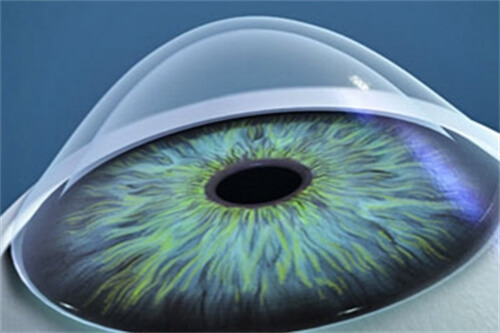

在高度近视并发症治疗方面,孙医生采用个性化方案,针对黄斑裂孔、视网膜劈裂等病变开展精密手术干预。